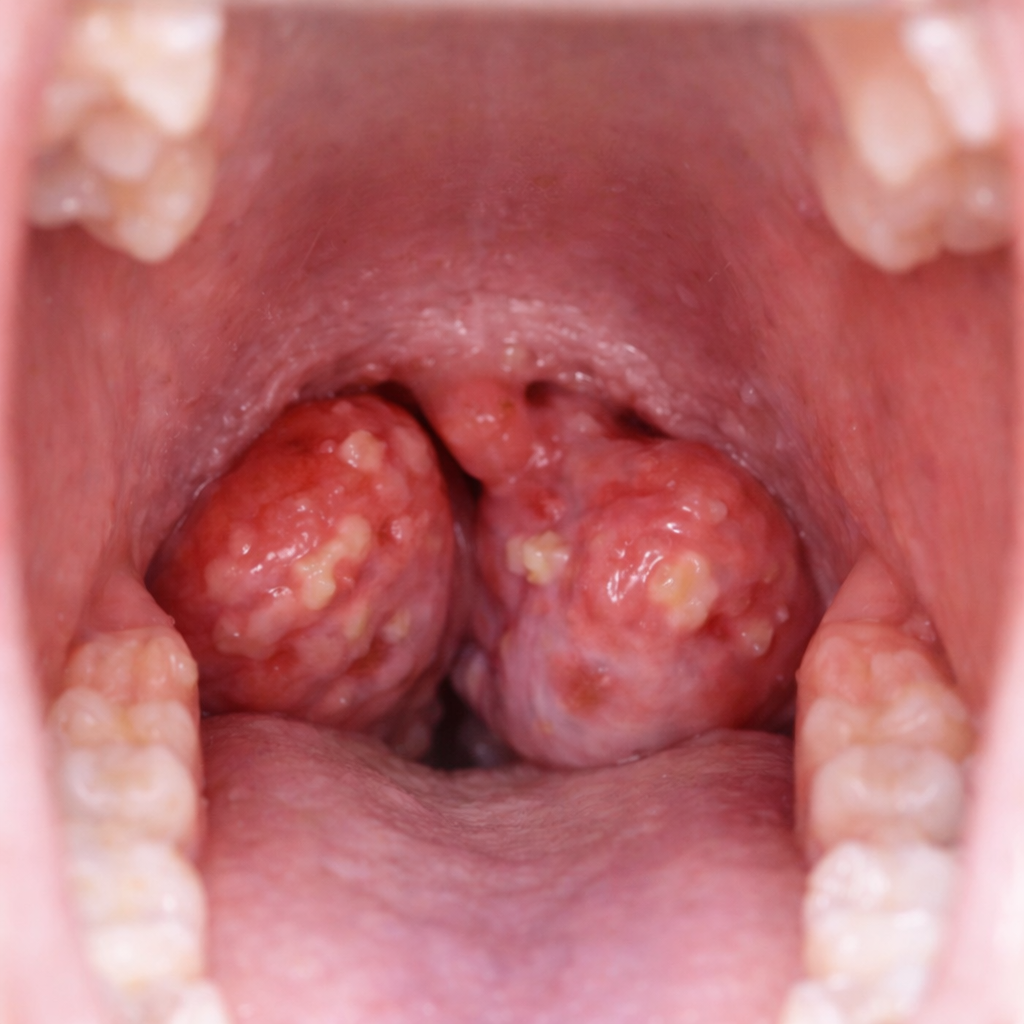

Tonsil and Adenoid Surgery in Singapore

Safe and effective treatment for recurring throat infections, snoring, and breathing issues in both children and adults.

Surgery to remove adenoids and tonsils is a safe and effective option for people who suffer from repeated throat infections, snoring, nasal obstruction, or breathing problems. The tonsils and adenoids are part of the immune system. However, if they become swollen or infected often, they may begin to cause more harm.

Tonsils are soft tissues located on each side of the back of the throat. Adenoids are located behind the nose, above the roof of the mouth. Both are part of the body’s defence system, helping to trap bacteria and viruses that enter through the mouth and nose.

In some cases, these tissues become inflamed, infected, or enlarged. This can lead to problems such as sore throats, tonsil stones (tonsilloliths), bad breath (halitosis), breathing difficulties, nasal blockage, poor sleep, sleep-disordered breathing, and obstructive sleep apnoea, affecting performance and quality of life. If these symptoms occur regularly, your ENT doctor may recommend surgery to remove adenoids and tonsils as a permanent solution.

Palatine Tonsils

Palatine tonsils are the type most commonly recognised by people. They are found on each side at the back of your throat. These tonsils help fight infection, but can become swollen or infected.

- Located on the left and right sides of the throat

- Easily seen when you open your mouth

- Commonly removed during tonsil surgery